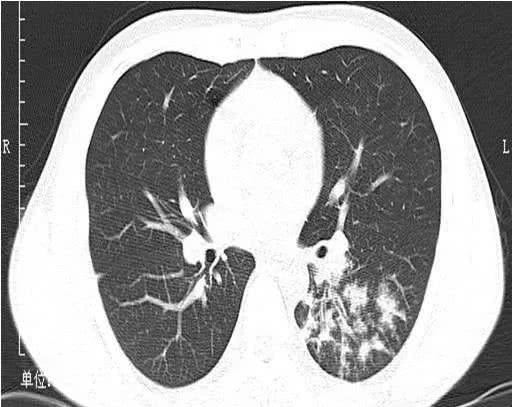

病毒性肺炎丨ct表现,诊断要点_小叶

② 小叶性肺炎